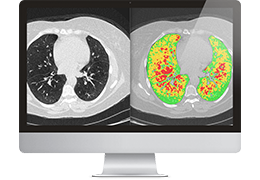

ART-Plan™ Artificial Intelligence Contouring